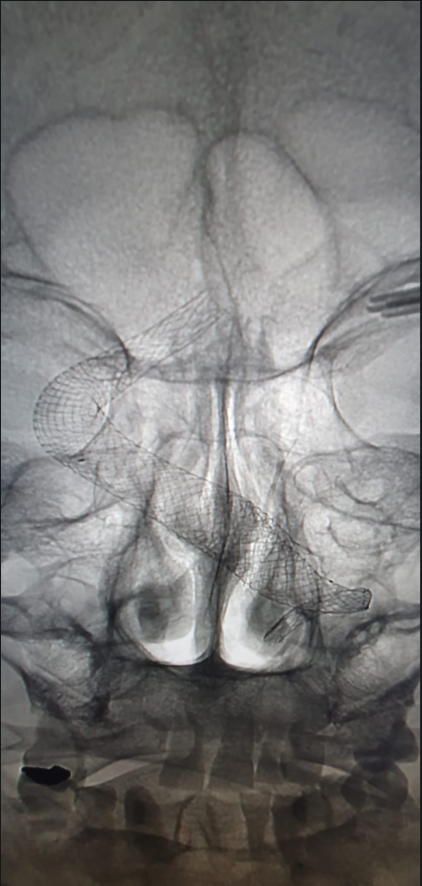

Pracoviště intervenční radiologie Nemocnice České Budějovice, a.s., slaví mimořádný úspěch. Vedoucí lékař MUDr. Jindřich Sova provedl se svým týmem jako první v republice náročný zákrok. Do gigantické výdutě mozkové tepny v blízkosti mozkového kmene endovaskulárně zavedl nově vyvinutý stent.

„Přijali jsme pacienta, kterému byla před pěti lety diagnostikovaná obrovská a tvarově složitá výduť (aneurysma) na mozkové tepně. Původně měl být operován otevřeně. Při diskusi ohledně postupu léčby kolega MUDr. Roman Klus navrhl řešení, se kterým se seznámil v rámci stáže na renomovaném pracovišti v Německu. Tímto řešením je implantace novinky, tzv. velkoformátového stentu – speciální výztuže, která se cévou zavádí přímo do výdutě. Stent eliminuje riziko jejího prasknutí a zároveň umožňuje dostatečné krevní zásobení dalších cév v okolí výdutě. Na základě pozitivní zkušenosti německých kolegů jsme se rozhodli pro stejný postup. V našem případě jsme implantovali stenty dva, vzhledem k velké délce aneurysmatu. Jednalo se o technicky velmi náročný zákrok, který již vyžadoval velkou zkušenost,“ popisuje MUDr. Sova.

Samotnému dvouhodinovému výkonu předcházela dvoudenní intenzivní příprava ve spolupráci s výrobcem stentu, včetně 3D modelace výdutě. „Jsme rádi, že zákrok proběhl úspěšně a pacient mohl být propuštěn domů. Je to pro nás nejen radost, ale i závazek do budoucna,“ doplňuje MUDr. Sova.